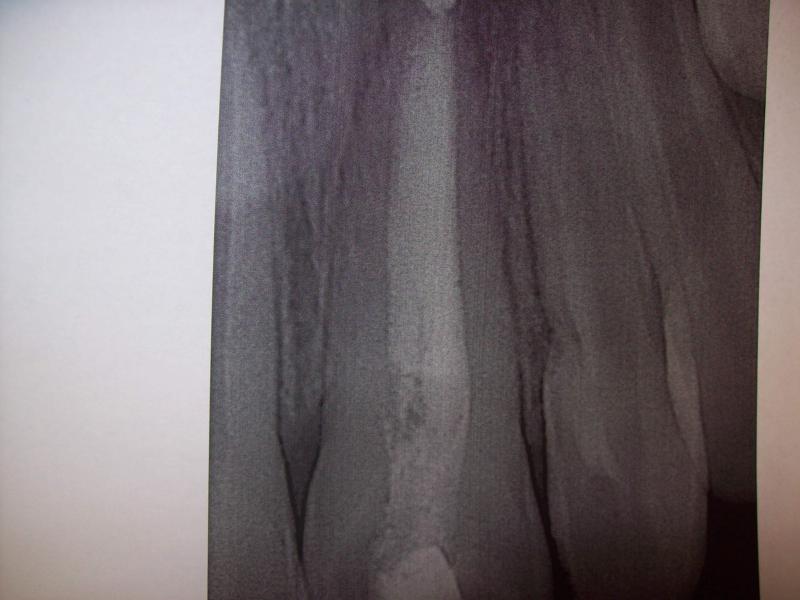

DR JET LOVES ROOT CANALS

General Dentist,  Performs Root Canals ONLY - Microscope Trained Dentist

"DR. JET'S MISSION IS TO PERFORM  ROOT CANALS FOR A REDUCED FEE USING THE LATEST TECHNOLOGY  AND TECHNIQUES TO SERVICE THE MANY PEOPLE WHO ARE UNINSURED OR UNDER-INSURED GIVING EVERYONE AN OPPORTUNITY TO SAVE THEIR TOOTH!"